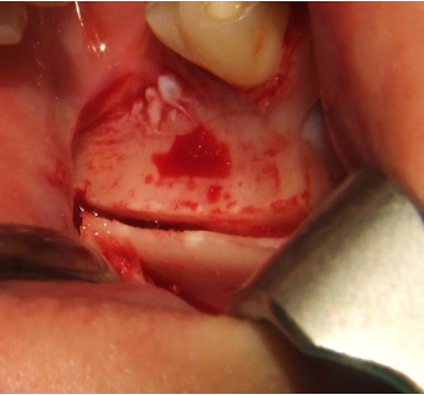

To access the ramus area, the concavity formed by the border between the ascending ramus and the external oblique ridge was identified and used as a starting point for the mucosal incision. The incision was made medial to the external oblique ridge and extended mesially toward the buccal aspect of the second molar. Care was taken to ensure that the incision was not extended too far lingually, preventing damage to structures on the lingual aspect of the mandible. A mucoperiosteal flap was elevated, exposing the lateral aspect of the ramus. The osteotomy was carried out with an osteotomy kit for PIEZOSURGERY® (Mectron, Germany) and was started anterior to the coronoid process at a point with adequate bone thickness. A micro reciprocating saw was used to cut through the cortex along the anterior border of the ramus medial to the external oblique ridge. The anterior vertical cut was made in the mandibular body in the molar region with a vertical saw. The length of this cut was dependent on the size requirements of the graft and on the position of the inferior alveolar canal. The posterior vertical cut was made on the lateral aspect of the ramus, perpendicular to the external oblique osteotomy. The inferior osteotomy connecting the posterior and anterior vertical cuts was made with a straight saw. This was a shallow cut into the ramus to create a line of fracture (Figure 2 [Fig. 2]).

Figure 2: The cranial cut through the cortex is placed on the lateral aspect of the left ramus and the anterior vertical cut was made in the mandibular body in the third molar region in order to harvest the bone graft.